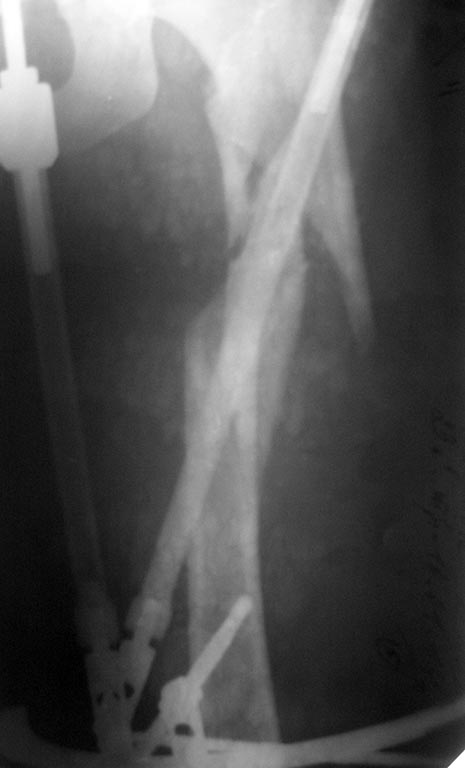

Рекомендации она не соблюдала: нагрузку на ногу начала недели 3 назад.

Сейчас беспокоят боли в одноименном коленном суставе, отека нет, болей в

месте перелома нет, анализы в норме, незначительное ограничение движений

в ТБС. По месту жительства выполнила КТ (снимки и описание в

приложении). Местные коллеги утверждают, что необходимо сделать

реостеосинтез, но сами не берутся. Вопрос больше от пациентки: "Делать

ли повторную операцию сейчас, или некоторое время походить с полной

нагрузкой и сделать контроль, а там решать?"